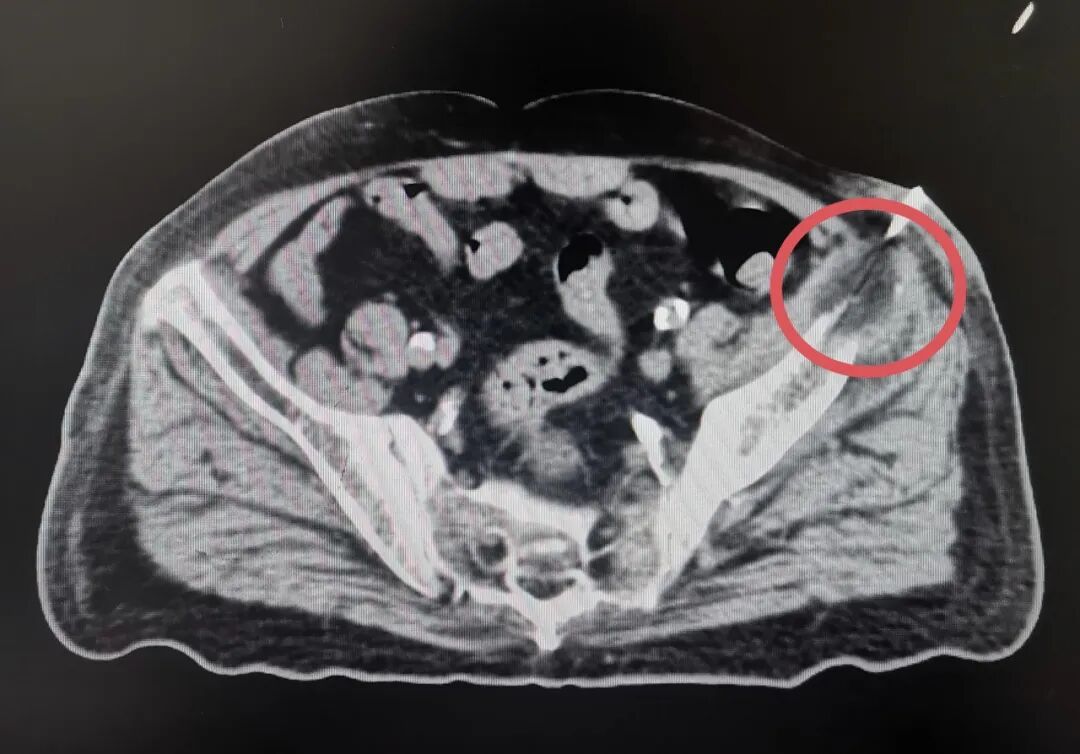

术中髋部CT影像

(红圈内为消融后病灶被冰球包裹)